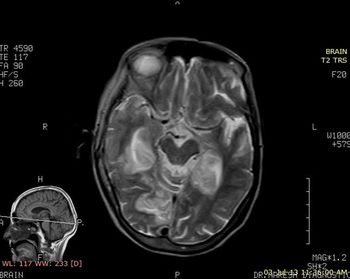

Case History: 42-year-old patient presents with complaints of headache.